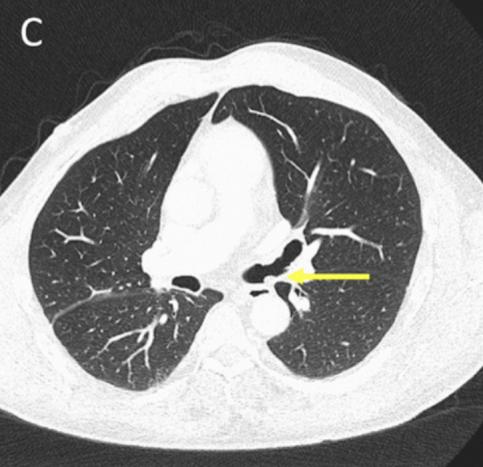

图2. 支气管镜影像CT检查怀疑恶性肿瘤

CT检查示右后上叶实变,没有看到含气支气管影,怀疑是支气管内肿瘤导致阻塞后实变(图1 A)。支气管内膜异常也出现在中间支气管和左主支气管(图1B、1C)。支气管镜检查显示,左侧主支气管、右侧中间支气管和右上叶后段支气管有大量息肉样肿块。(图2)